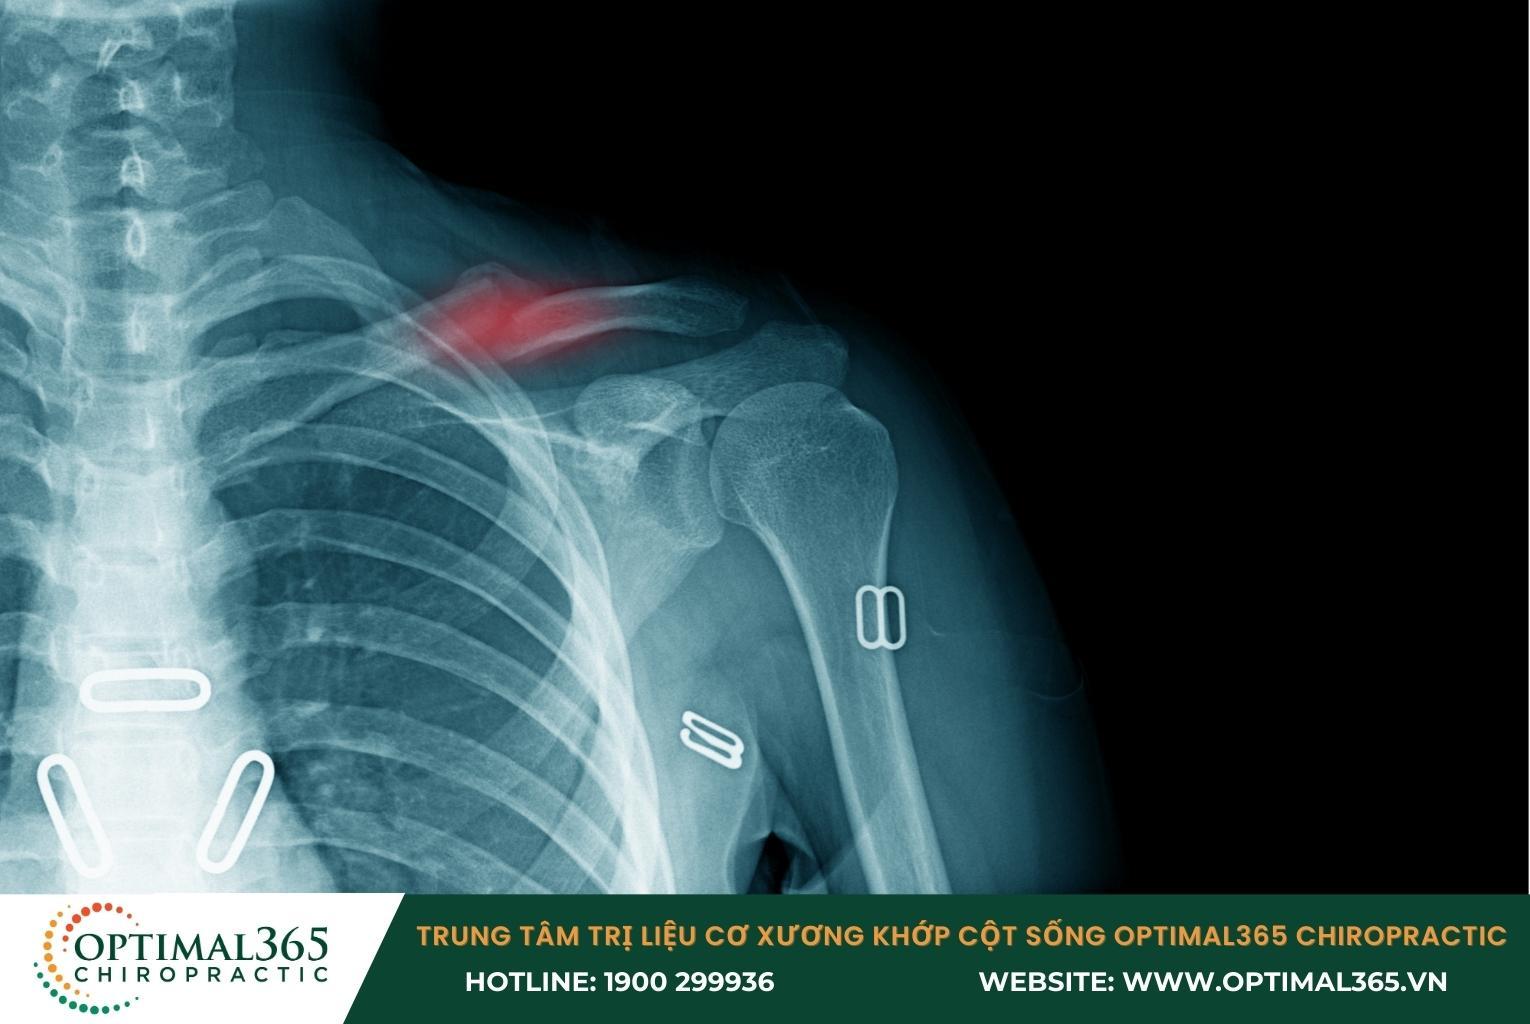

Gãy xương bả vai

Lực tác động mạnh do té ngã, tai nạn có thể làm xương bả vai bị rạn nứt hoặc gãy. Loại chấn thương vai này dễ xảy ra nhất ở phần đầu hoặc phần thân của xương cánh tay và xương đòn.

Các triệu chứng đặc trưng của tình trạng gãy xương bả vai là:

- Đau đớn tại vị trí gãy, cơn đau nhanh chóng lan tỏa khắp phần bả vai.

- Sưng to và bầm tím khu vực khớp vai.

- Khó khăn khi nhấc cánh tay lên, có tiếng động rắc rắc khi di chuyển khớp vai.

- Có thể nhìn thấy hoặc chạm thấy phần đầu xương nhô lên khỏi da.